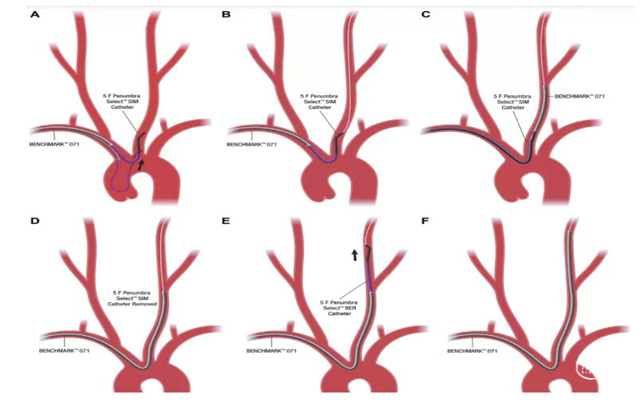

经对侧桡动脉置6F动脉鞘,行对侧低位椎动脉支架置入示意图:

2、可选择对侧桡动脉置入6F动脉鞘,单弯或西蒙导管将0.035泥鳅导丝置于病灶侧锁骨下动脉起到牵拉作用。

3、将6F导引导管到达狭窄椎动脉附近,微导丝导引球囊扩张支架(4-5mm)铆定狭窄部位后扩张释放支架。

备注:6F导引导管可兼容0.035 in泥鳅导丝和球囊扩张支架(4-5mm),5mm支架通过略涩。